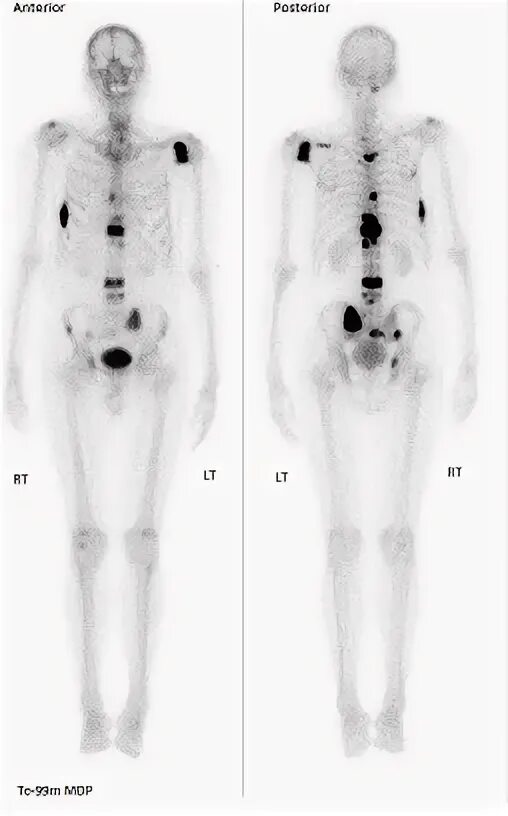

Метастазы костей скелета